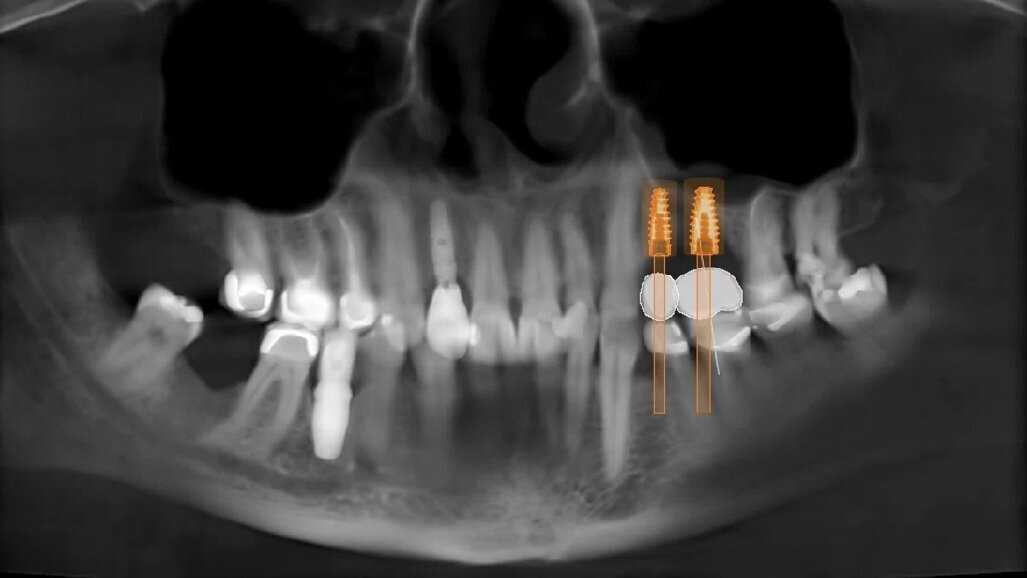

Fig. 10_Pianificazione finale in visione Panorex.

Appare quindi chiaro come eseguire una valutazione pre-operatoria in ambiente digitale ci permetta di prendere in esame una grande quantità di parametri che in passato erano lasciati alla sensibilità ed all’esperienza dell’operatore (Fig. 10). Eseguire questo tipo di valutazione tuttavia non è affatto complesso, oggi per la pianificazione di un caso di elevazione del seno mascellare è già gold standard richiedere una CBCT dell’arcata dentale superiore estesa al COM e gli unici step da aggiungere sono: il rilevamento di una scansione digitale intra-orale (o impronta analogica tradizionale che verrebbe acquisita e digitalizzata in laboratorio) e la realizzazione di una ceratura diagnostica virtuale con l’obiettivo di accoppiare queste informazioni con il dato radiologico CBCT all’interno di un software specifico che consenta la progettazione del caso. Sfruttando tali strumenti possiamo essere quindi in grado di fornire ai nostri pazienti risultati più predicibili ed inoltre evidenziare, prima di iniziare il trattamento, eventuali criticità avendo margine temporale e progettuale per correggerle.